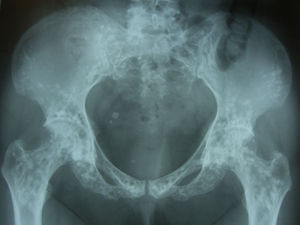

Diagnóstico y evoluciónEn la Rx que aportó la paciente se identificaron unos signos radiológicos que resultaron diagnósticos: numerosas imágenes radiopacas o esclerosas, pequeñas, homogéneas, bien definidas y circulares agrupadas en regiones periarticulares. Era un caso de osteopoiquilosis. No había manifestaciones clínicas con relación a esta enfermedad, tampoco se evidenciaron lesiones cutáneas. Se trataba de un hallazgo casual. A esta paciente se le solicitaron Rx de hombros, manos, pelvis, rodillas y pies (figs. 1–4), y se pudo comprobar que las lesiones halladas en el codo también estaban presentes en todas estas localizaciones. La osteopoiquilosis suele afectar a epífisis y metáfisis de huesos tubulares largos, carpo, tarso, pelvis y escápula de forma simétrica. El tamaño de las lesiones es uniforme.

DiscusiónLa osteopoiquilosis u osteopatía condensante diseminada es una displasia osteosclerótica asintomática. Su aparición antes de los 3 años es infrecuente, aparece tanto en varones como en mujeres. Existen casos hereditarios y esporádicos. Las manifestaciones clínicas suelen faltar, aunque en un 25% de casos pueden encontrarse lesiones cutáneas que consisten en infiltraciones fibrocolágenas, predisposición a la formación de queloides y lesiones similares a las de la esclerodermia. Los hallazgos radiológicos son diagnósticos1. El diagnóstico diferencial debe hacerse con metástasis osteoblásticas, mastocitosis y esclerosis tuberosa2. La distribución simétrica, la afectación de epífisis y metáfisis, y el tamaño uniforme de las lesiones son datos sugestivos de osteopoiquilosis. El aspecto normal de una gammagrafía ósea acabaría de apoyar el diagnóstico.